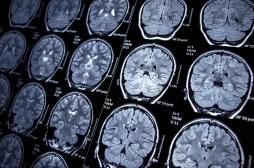

hippocampe